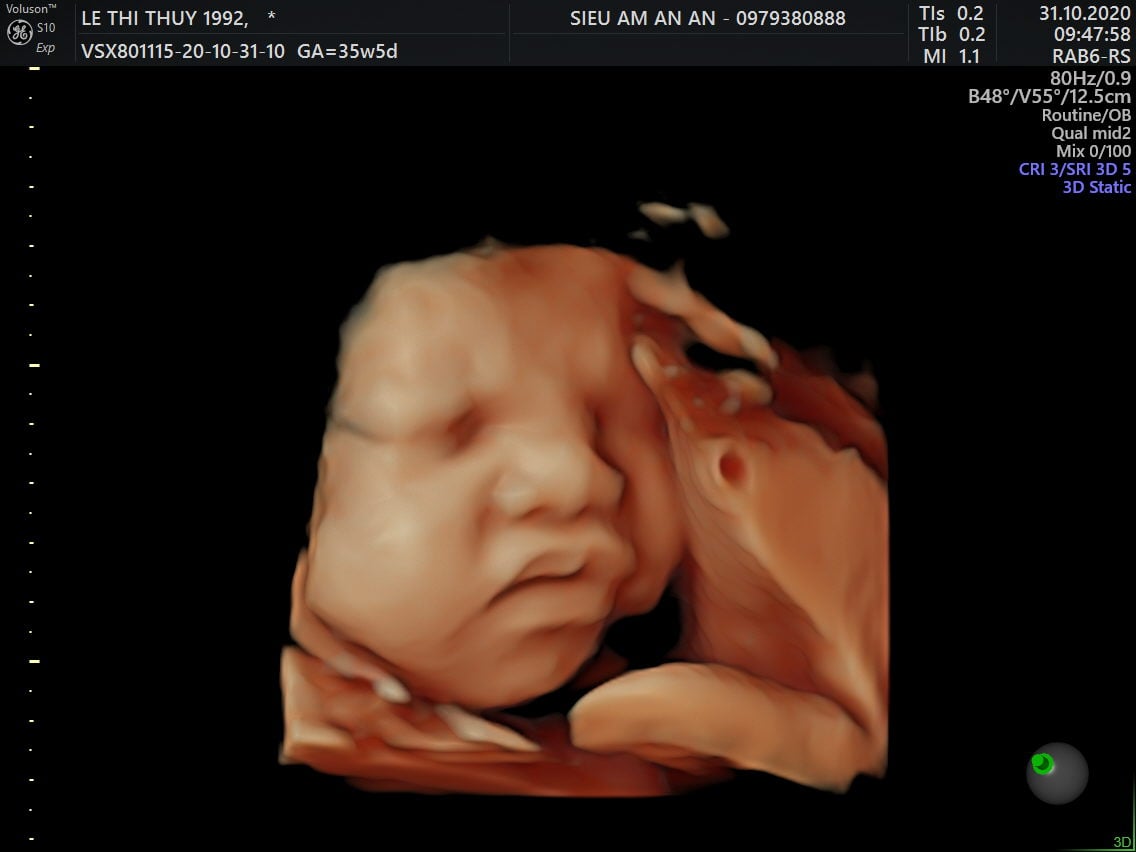

Thai nhi 36 tuần phát triển như thế nào? Ăn gì để con tăng cân, thai 36 tuần gò nhiều, thai 36 tuần nặng bao nhiêu là chuẩn? Qua siêu âm, mẹ có thể thấy hình ảnh một bé yêu mũm mĩm đáng yêu rất giống với em bé sơ sinh hoàn chỉnh. Điều này khiến nhiều mẹ thấy trái tim mình như tan chảy, bé yêu dường như đang đến rất gần rồi.

Chỉ còn khoảng 4 tuần nữa em bé sẽ chào đời, mẹ chắc chắn đang rất tò mò về sự phát triển của bé ở giai đoạn này. Khi mang thai tuần 36, mẹ dễ dàng theo dõi được hình thái của bé qua siêu âm. Các bộ phận chân, tay cử động nhẹ nhàng vô cùng đáng yêu. Hình ảnh mũm mĩm, mập mạp của bé thật sự khiến trái tim mẹ nào cũng phải tan chảy.

Ngược lại, nếu cơn gò nhiều đi kèm các triệu chứng ra máu, vỡ ối, rò rỉ ối, chóng mặt, ngất xỉu, đau liên tục, mẹ cần đến bệnh viện kiểm tra sức khỏe càng sớm càng tốt. Rất có thể mẹ đang đối mặt với hiện tượng sinh non. Qua hình ảnh thai nhi 36 tuần từ máy siêu âm, bác sĩ sẽ đưa ra chỉ định tối ưu nhất.